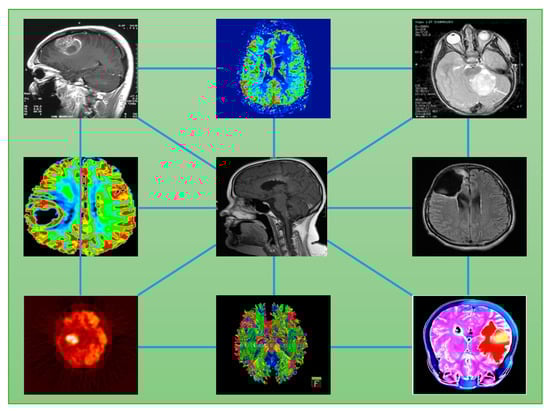

6. From Images to Networks

Cancer heterogeneity implies complexity for which in-depth analysis is needed. The first consideration concerns the scale factor. Heterogeneity is present at various levels: genetic, molecular, cellular, and physiological, among others, which obviously leads to the search for a multiscale inference approach. This way, a blend of image readout information can be integrated into interpretable models as a mix of physiological properties such as perfusion, oxygenation, pH, and hypoxia; anatomical structure; histological characterization (necrotic, viable, angiogenic, etc.); molecular profile; phenotypic disease expression (intra-patient sub-clonality etc.); and more. Defining the stage of a tumor requires accounting for all such aspects, measuring and quantifying them in a way suitable to represent tumor states. However, data features gathered at a variety of spatio-temporal resolutions are hard to integrate into an interpretable predictive model (Figure 2) [49].

Figure 2. Image features integration from different imaging modalities.